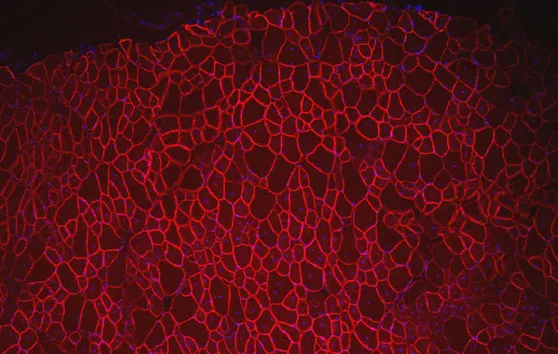

GSK a annoncé une amélioration significative de la marche chez les malades souffrant de myopathie de Duchenne traités durant un an avec le drisapersen qui favorise un saut d’exon ; un essai de phase II auquel l’Institut de Myologie a collaboré.

Amélioration significative de la marche chez les malades atteints de myopathie de Duchenne (DMD) traités 12 mois par drisapersen.